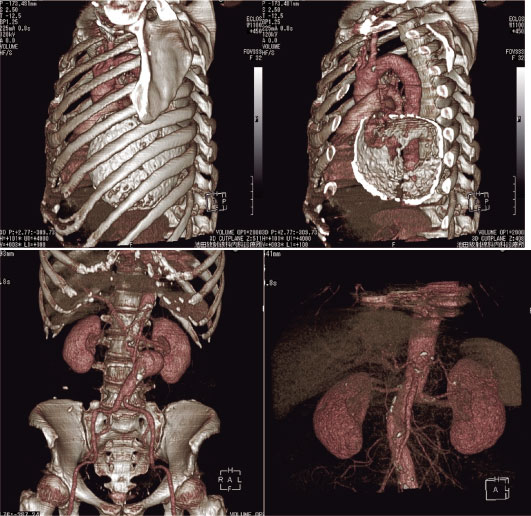

画像 3 上段左は膵体部の嚢胞性病変。右は右水腎症及び後腹膜線維症疑い。

下段左右は同一症例で上行結腸憩室炎及び背側を上行する虫垂をとらえたもの。

Voxel transmission法で処理後前腹壁から切削。